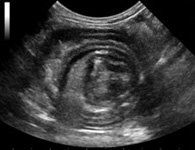

Ecografia

Presso il Centro Veterinario Imperiese è attivo un servizio di ecografia: in sale dedicate, sono disponibili due ecografi di ultima generazione MyLab Class e My Lab 30, strumenti moderni mediante i quali è possibile eseguire ecografie, ecocardiografie, studi Doppler, Doppler tissutale, esami ecografici con mezzi di contrasto e tecniche interventistiche ecoguidate, la disponibilità di 7 sonde elettroniche permette l’esecuzione di esami con elevati standard di qualità in animali di tutte le dimensioni.

Questo servizio è attivo tutti i giorni su appuntamento per il clienti della clinica e per i colleghi che intendono usufruirne, gli esami vengono immediatamente refertati su supporto digitale consegnato al proprietario e comunicato mediante mail al veterinario curante.

Ecografia addominale

Gli ultrasuoni sono un ausilio fondamentale per lo studio di tutti gli organi addominali, è uno degli esami necessari per la gestione di pazienti con malattie di competenza medica e chirurgica che possono colpire frequentemente i nostri pazienti.

Numerosi sono i vantaggi: è una metodica indolore, ripetibile e non necessita quasi mai di anestesia; può essere un ausilio fondamentale per eseguire ago-aspirati, biopsie o altre tecniche interventistiche eco-guidate.